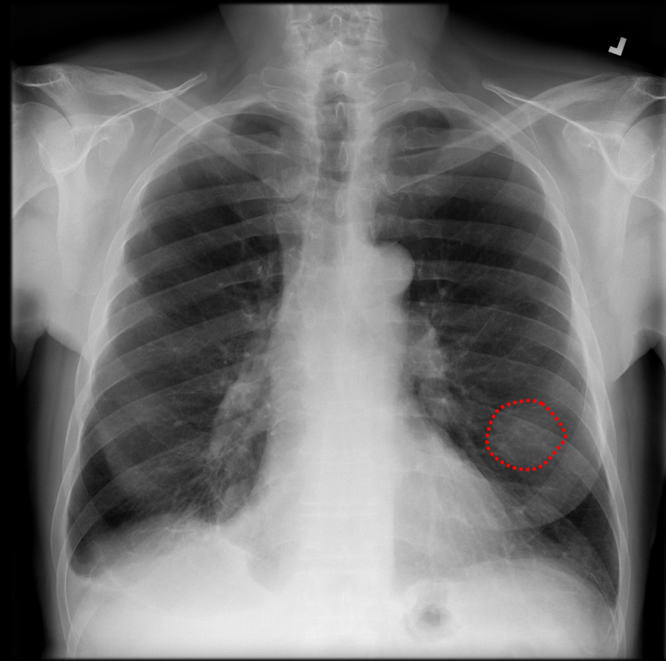

DEFINING MAJOR ABNORMALITIES IN CHEST XRAY

AIRA Chest, a computer-aided diagnosis software to assist radiologists in accurately detecting lung masses, cardiomegaly, consolidation, and pneumothorax. This AI-powered solution generates tumor locations as region of interest or heatmaps, along with an abnormality severity score indicating the probability of abnormality. Designed for use as a second opinion tool in the initial interpretation process by physicians, AIRA Chest aims to boost confidence and reduce false negatives (Type II Error) associated with AI solutions. AIRA's goal is to facilitate validated diagnoses, prevent missed cases, and enable trainee radiologists to perform at a specialist level in detecting chest abnormalities.